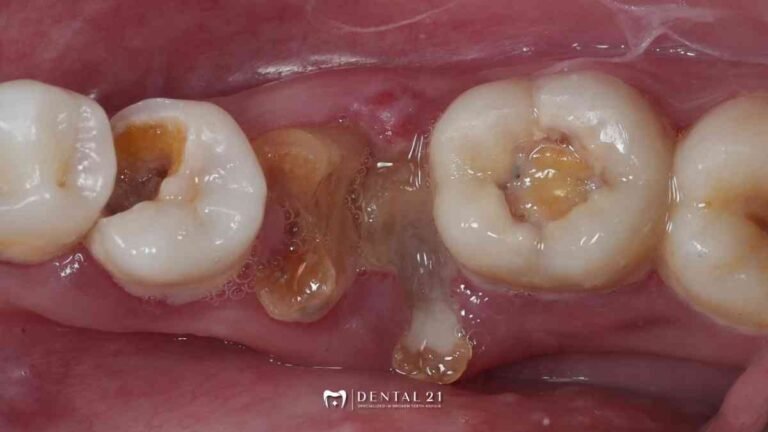

Dentist PIK untuk Gigi Rusak Parah: Tambal, PSA, atau Crown? Ini Cara Menentukannya Saat Anda mencari dentist PIK untuk menangani gigi rusak parah, sering kali muncul pertanyaan: apakah kondisi ini cukup ditambal, perlu PSA (perawatan saluran akar), atau bahkan memerlukan…